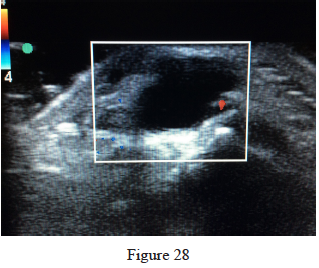

28. Figure 28 is the ultrasound of a 23-year-old patient who has had a volar radial 1.5-cm tender and painful wrist mass for 6 months. The additional workup prior to surgery should consist of